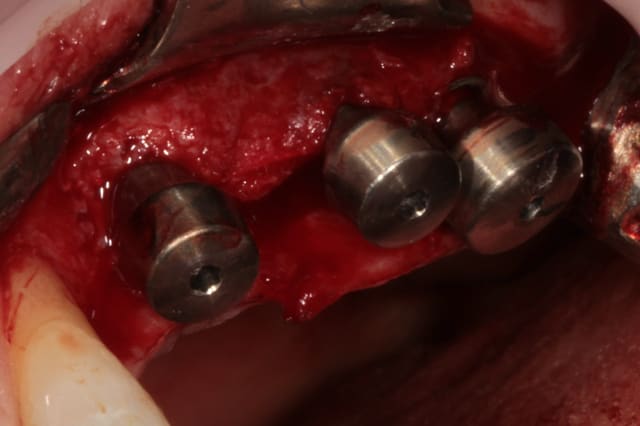

et un et deux et trois

D1 pour "assouplir"

éponge

implant lisse conique

éponge...